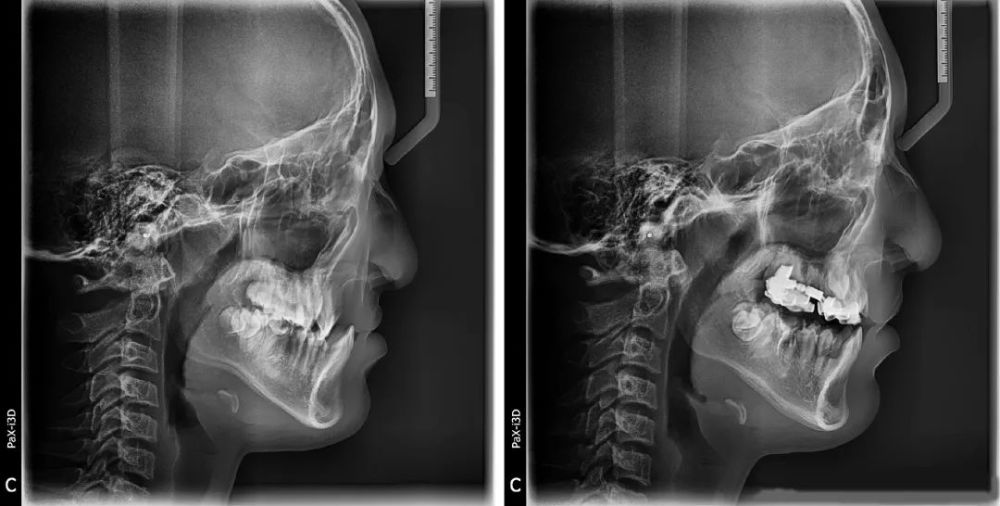

动图是严重骨性III类畸形上颌骨发育不足的患者,刺激颌骨生长前后的效果对比。

单纯正畸治疗,没有正颌哦~

以下是没画轮廓的原图

效果是不是很明显?做完矫正真的好看了很多呢~